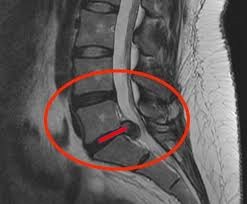

Se você convive com dor na coluna há meses ou anos, já tentou tratamentos, exames e orientações diferentes, e mesmo assim a dor volta, este espaço é para você. A dor persistente não surge porque você é fraco, sedentário ou “fez algo errado”. Na maioria dos casos, ela permanece porque o problema nunca foi compreendido em profundidade. Aqui, o foco não é apenas aliviar sintomas. É entender por que a dor continua.

O quiropraxista avalia detalhadamente a postura, a história clínica e as condições específicas de cada paciente. Em seguida, utiliza técnicas manuais chamadas “ajustes quiropráticos” para realinhar as articulações e aliviar a pressão sobre os nervos. O objetivo é restaurar a funcionalidade do corpo e permitir que ele se cure de forma natural.

Identificar na sua coluna desalinhamentos que precisem dos ajustes vertebrais que estão gerando dor e perda de movimento.